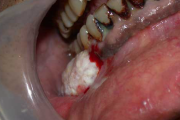

B vitamiini puudus